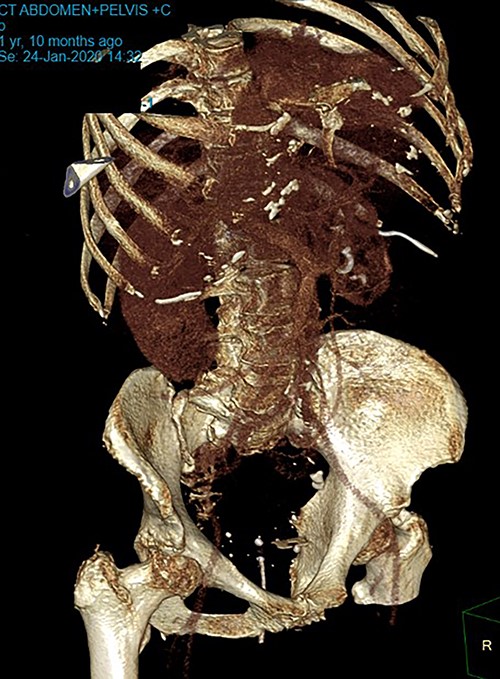

Patient SC is a 72-year-old lady who presented with urosepsis secondary to a left-sided distal ureteric renal stone. Her medical history includes ischemic heart disease, chronic pulmonary obstructive airway disease, type 2 diabetes mellitus, Parkinson’s disease and a previous open cholecystectomy. She was admitted to the intensive care unit and a left-sided nephrostomy tube was inserted. Initial CT imaging incidentally identified a ‘bread clip’-shaped FB in the distal jejeunum (Figs 1 and 2). There was no evidence of obstruction nor perforation. Abdominal X-rays failed to show the presence of a FB.

The acute surgical unit team consulted the patient and initial conservative management included keeping a stool diary and trialling 1 L of glycoprep. Unfortunately, serial imaging failed to show any meaningful progression of the FB. After a successful antegrade ureteric stent insertion, the patient recovered from urosepsis and a decision was made to proceed with a laparoscopic small bowel resection to retrieve the FB.

Intraoperatively, an inflamed segment of 5 cm of the mid jejunum was identified, the FB was palpable and appeared to be partially eroding through the serosa. A SB resection was performed with primary stapled anastomosis. The FB was identified as a BC.

Secondly, as shown in the three cases, unless the BC is calcified, abdominal plain films are not a reliable method of tracking nor diagnosing BC ingestion [9–13]. CT is more sensitive, with a sensitivity rate of 67%, but is not consistently reliable on its own [6, 7]. Reconstructed 3D imaging is effective in identifying BCs. Most BCs are made of low-density polystyrene, a type of versatile solid plastic, which are not readily identified on plain film imaging [14, 15]. This non-degradable plastic means that it is usually only a matter of time before a patient develops a complication.